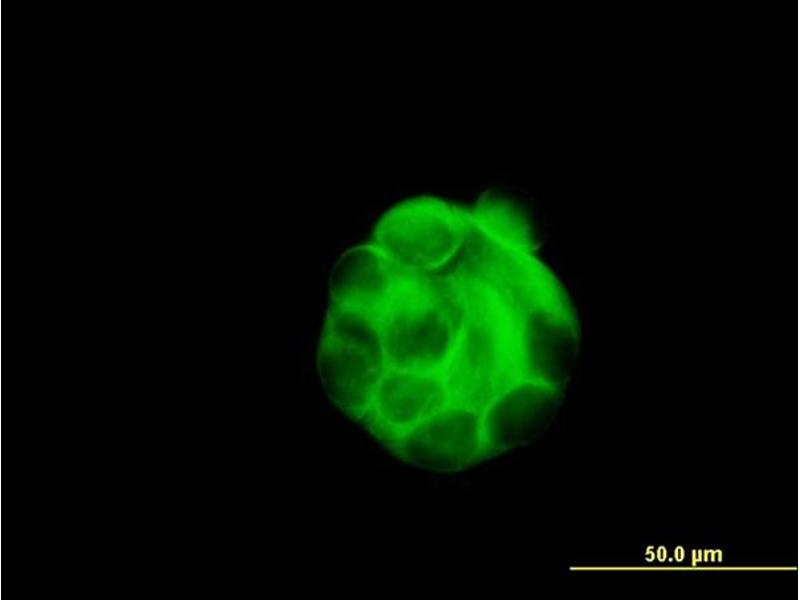

- Mouse monoclonal antibody raised against a partial recombinant SGCB.

- SGCB (NP_000223, 87 a.a. ~ 196 a.a) partial recombinant protein with GST tag. MW of the GST tag alone is 26 KDa.